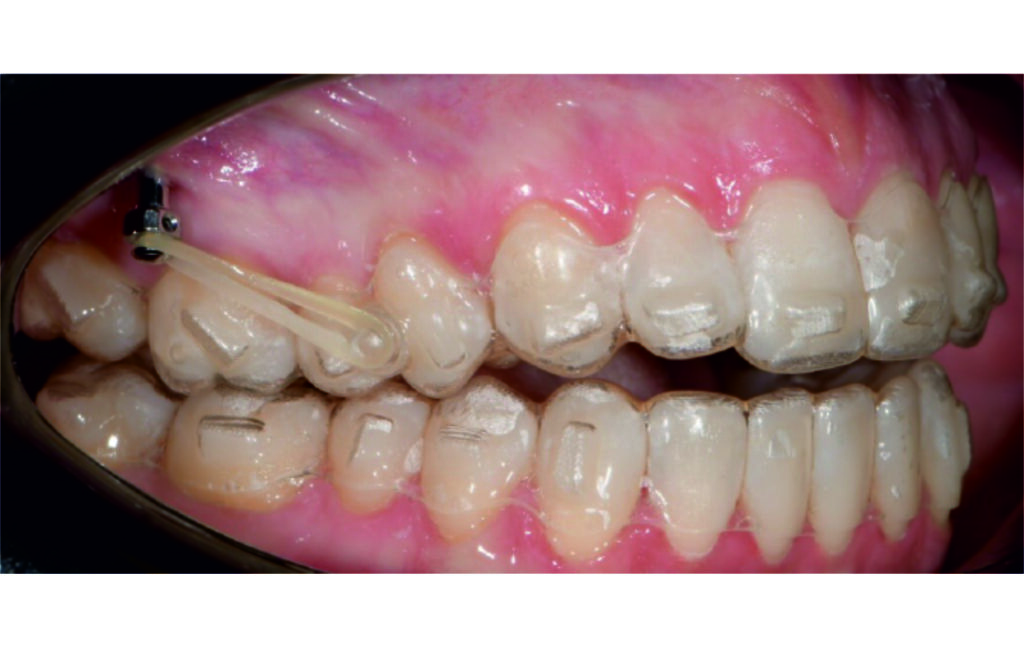

Vertical vector of elastic traction on buttons and IZC helped with the open bite correction.

No sequential distalization for Class II tendency correction was performed due to skeletal anchorage. Lingual attachments were used to improve aligner grip and control tooth movement, as small, angulated lower incisors are difficult to move due to limited anatomy.

An infrazygomatic crest (IZC) screw with force applied between the upper premolars produces a clockwise rotation of the maxillary occlusal plane. This movement aids in closing the anterior open bite and improves upper incisor display. IZC screws with elastics also enable planned intrusion of the upper molars by 1 mm. Because mandibular derotation after upper posterior correction is difficult to predict, anterior distalization and midline correction were performed in the later stages of treatment.